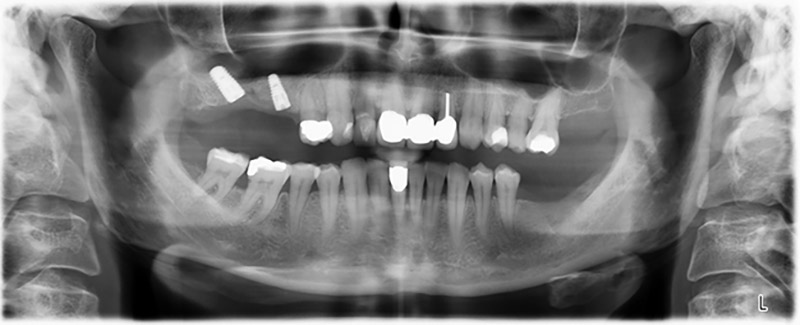

La paziente, 59 anni, presenta un caso di parodontite avanzata e descrive una sensazione di fastidio e scarsa sensibilità gustativa dal primo quadrante in direzione distale. L'esame clinico rivela tasche parodontali generalmente diffuse e un'atrofia ossea molto avanzata nelle regioni 16 e 14. L'esito è confermato dalla radiologia (fig. 1). Non è possibile salvare i denti 16 e 14.

Immagine 1: ortopantomografia con artrofia ossea nella regione 16–14. *